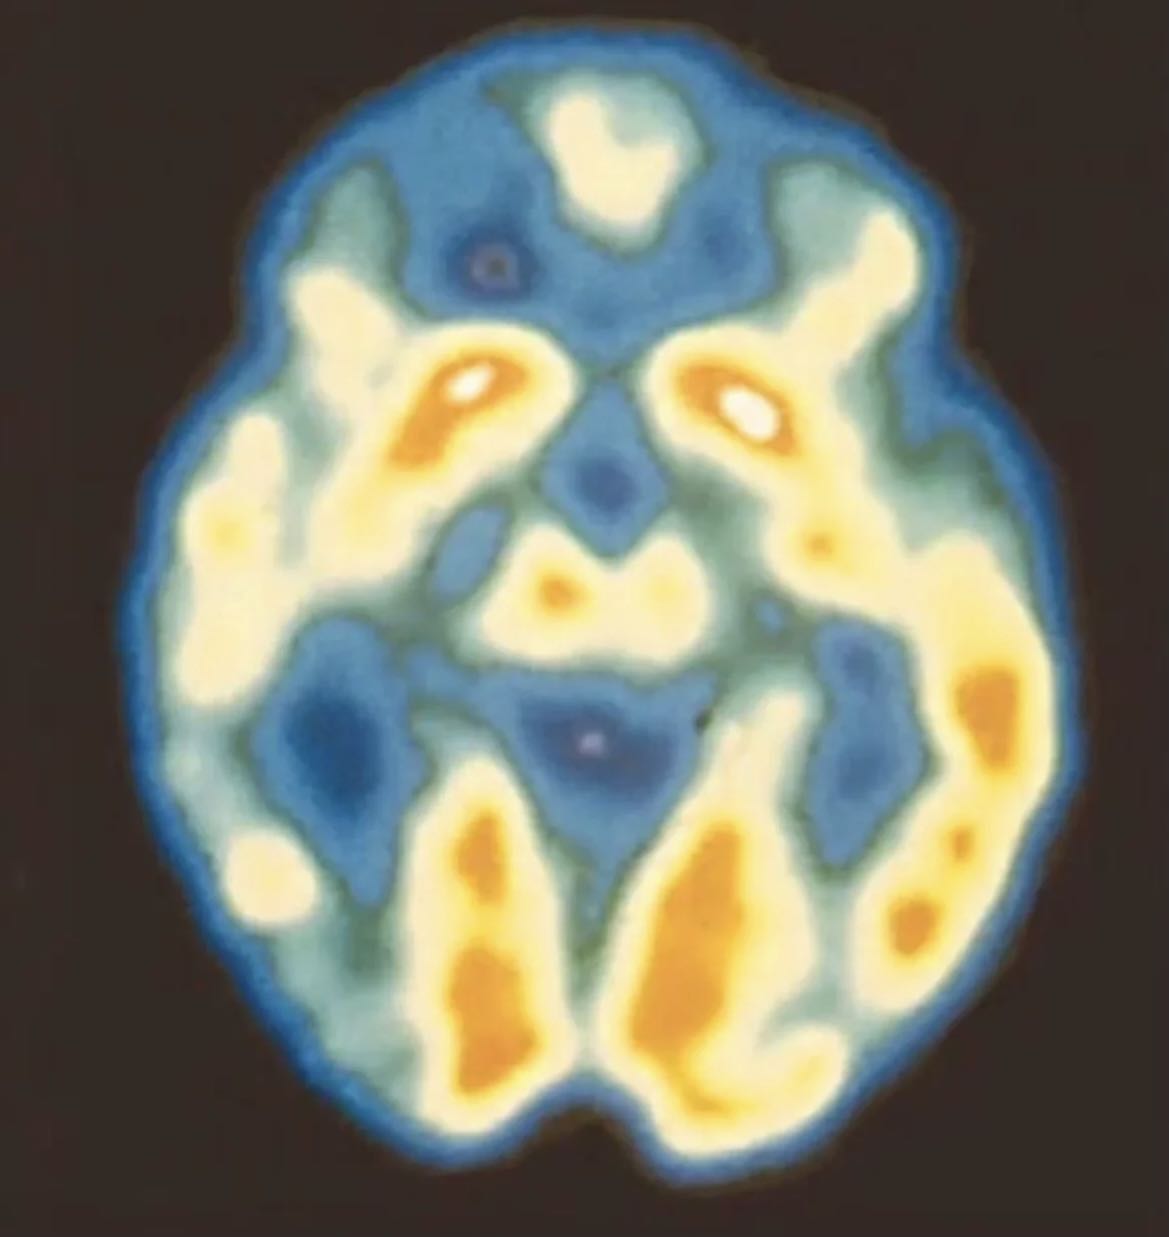

Bipolar Disorder(BD), also be called “genius disease”, is recognized as a mental illness that needs professional treatment. It is rather painful to live in the normal life for most patients. However, to Joyce, she doesn’t really regard it a disease that should be afraid of or eliminated; during the 7-year long process when co-exist with it, she found the best way to overcome the pain is to devote herself to the artwork creation, which is, to use another practical way to express, as well as make it poetic.

I used the pics of brain in health condition and in bipolar disorder condition via internet sources, and made the programme in TD to achieve this beautiful effect: